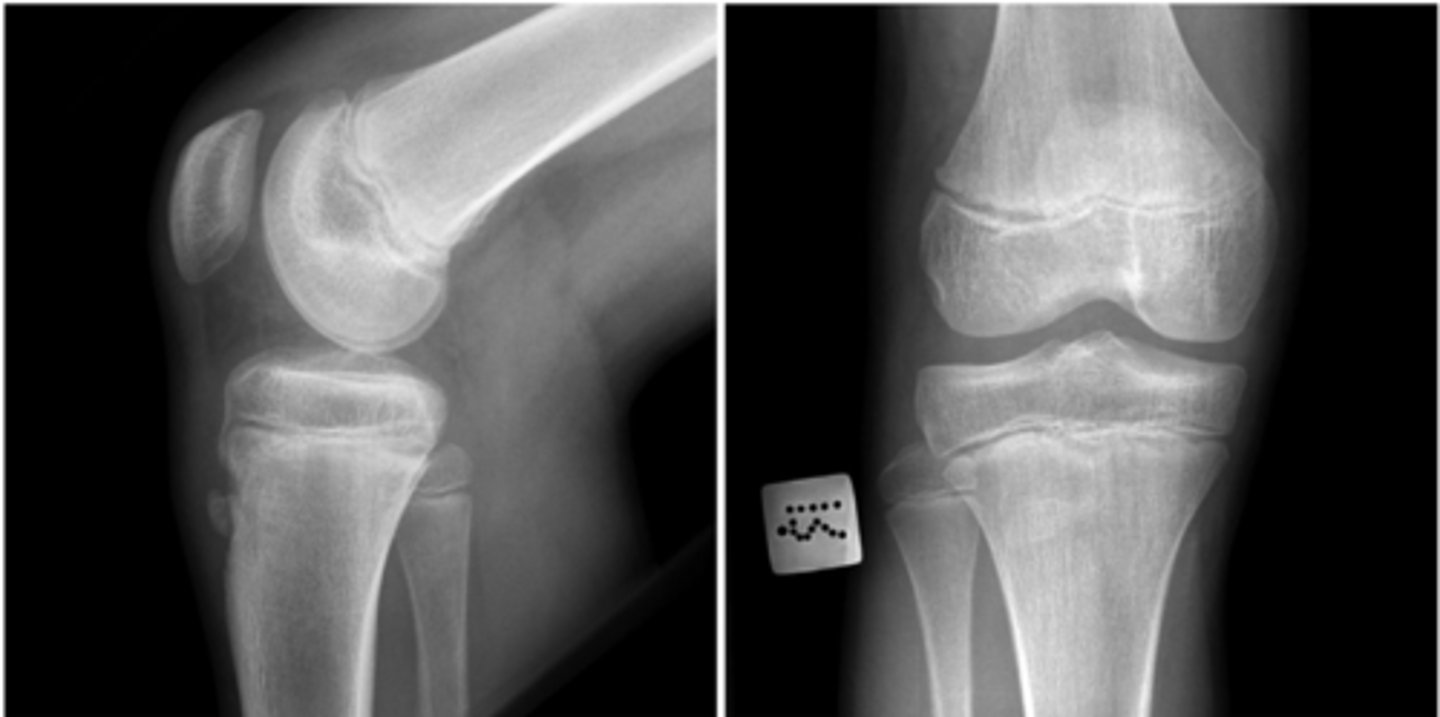

Radiographs showing inferior slip of proximal femoral metaphysis relative to epiphysis

**SCFE

A 13-year-old boy with no significant medical history presents to the pediatrician for evaluation of left knee pain. The pain has been ongoing for several weeks with no inciting incident but has worsened over the last few days. The patient’s parent notes they took him to urgent care overnight, and radiographs of the left knee were unremarkable. He is having pain with weight-bearing and is unable to walk into the office today. He was born via full-term vaginal delivery and is up to date on his childhood immunizations. He has had no preceding illness. Vital signs are a temperature of 98.0°F, heart rate of 96 bpm, blood pressure of 110/68 mm Hg, respiratory rate of 12 breaths/min, and oxygen saturation of 99% on room air. His body mass index is 34 kg/m2. Physical examination reveals erythema, no swelling, no tenderness to palpation of the knee, and a negative ligamentous examination. The leg appears shortened when compared to the other side and is held in external rotation. The patient has pain with motion of the hip, most notably internal rotation. Evaluation of the ankle and foot is unremarkable. Which finding is consistent with the most likely diagnosis?

CRadiographs showing inferior slip of proximal femoral metaphysis relative to epiphysis